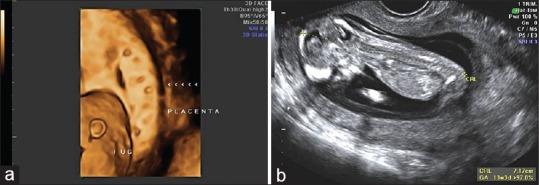

Partial/complete hydatidiform mole with coexisting fetus is a rare condition. Optimal management is a challenge that remains a dilemma since these pregnancies are associated with maternal as well as fetal complications including hemorrhage, preeclampsia, thromboembolic disease, intra uterine demise and increased risk of persistent trophoblastic disease. Here we report 2 cases of partial mole with live fetus after ICSI and a case of complete mole with coexisting fetus after ICSI in a turner mosaic that resulted in a live birth.

部分性/完全性葡萄胎合并存活胎儿是一种罕见情况。最佳管理是一项挑战,仍然是一个两难困境,因为这些妊娠与母体和胎儿并发症相关,包括出血、先兆子痫、血栓栓塞性疾病、宫内死亡以及持续性滋养细胞疾病风险增加。在此,我们报告2例经卵胞浆内单精子注射(ICSI)后部分性葡萄胎合并存活胎儿的病例,以及1例经ICSI后完全性葡萄胎合并存活胎儿的病例,该病例为特纳综合征嵌合体,最终成功分娩。